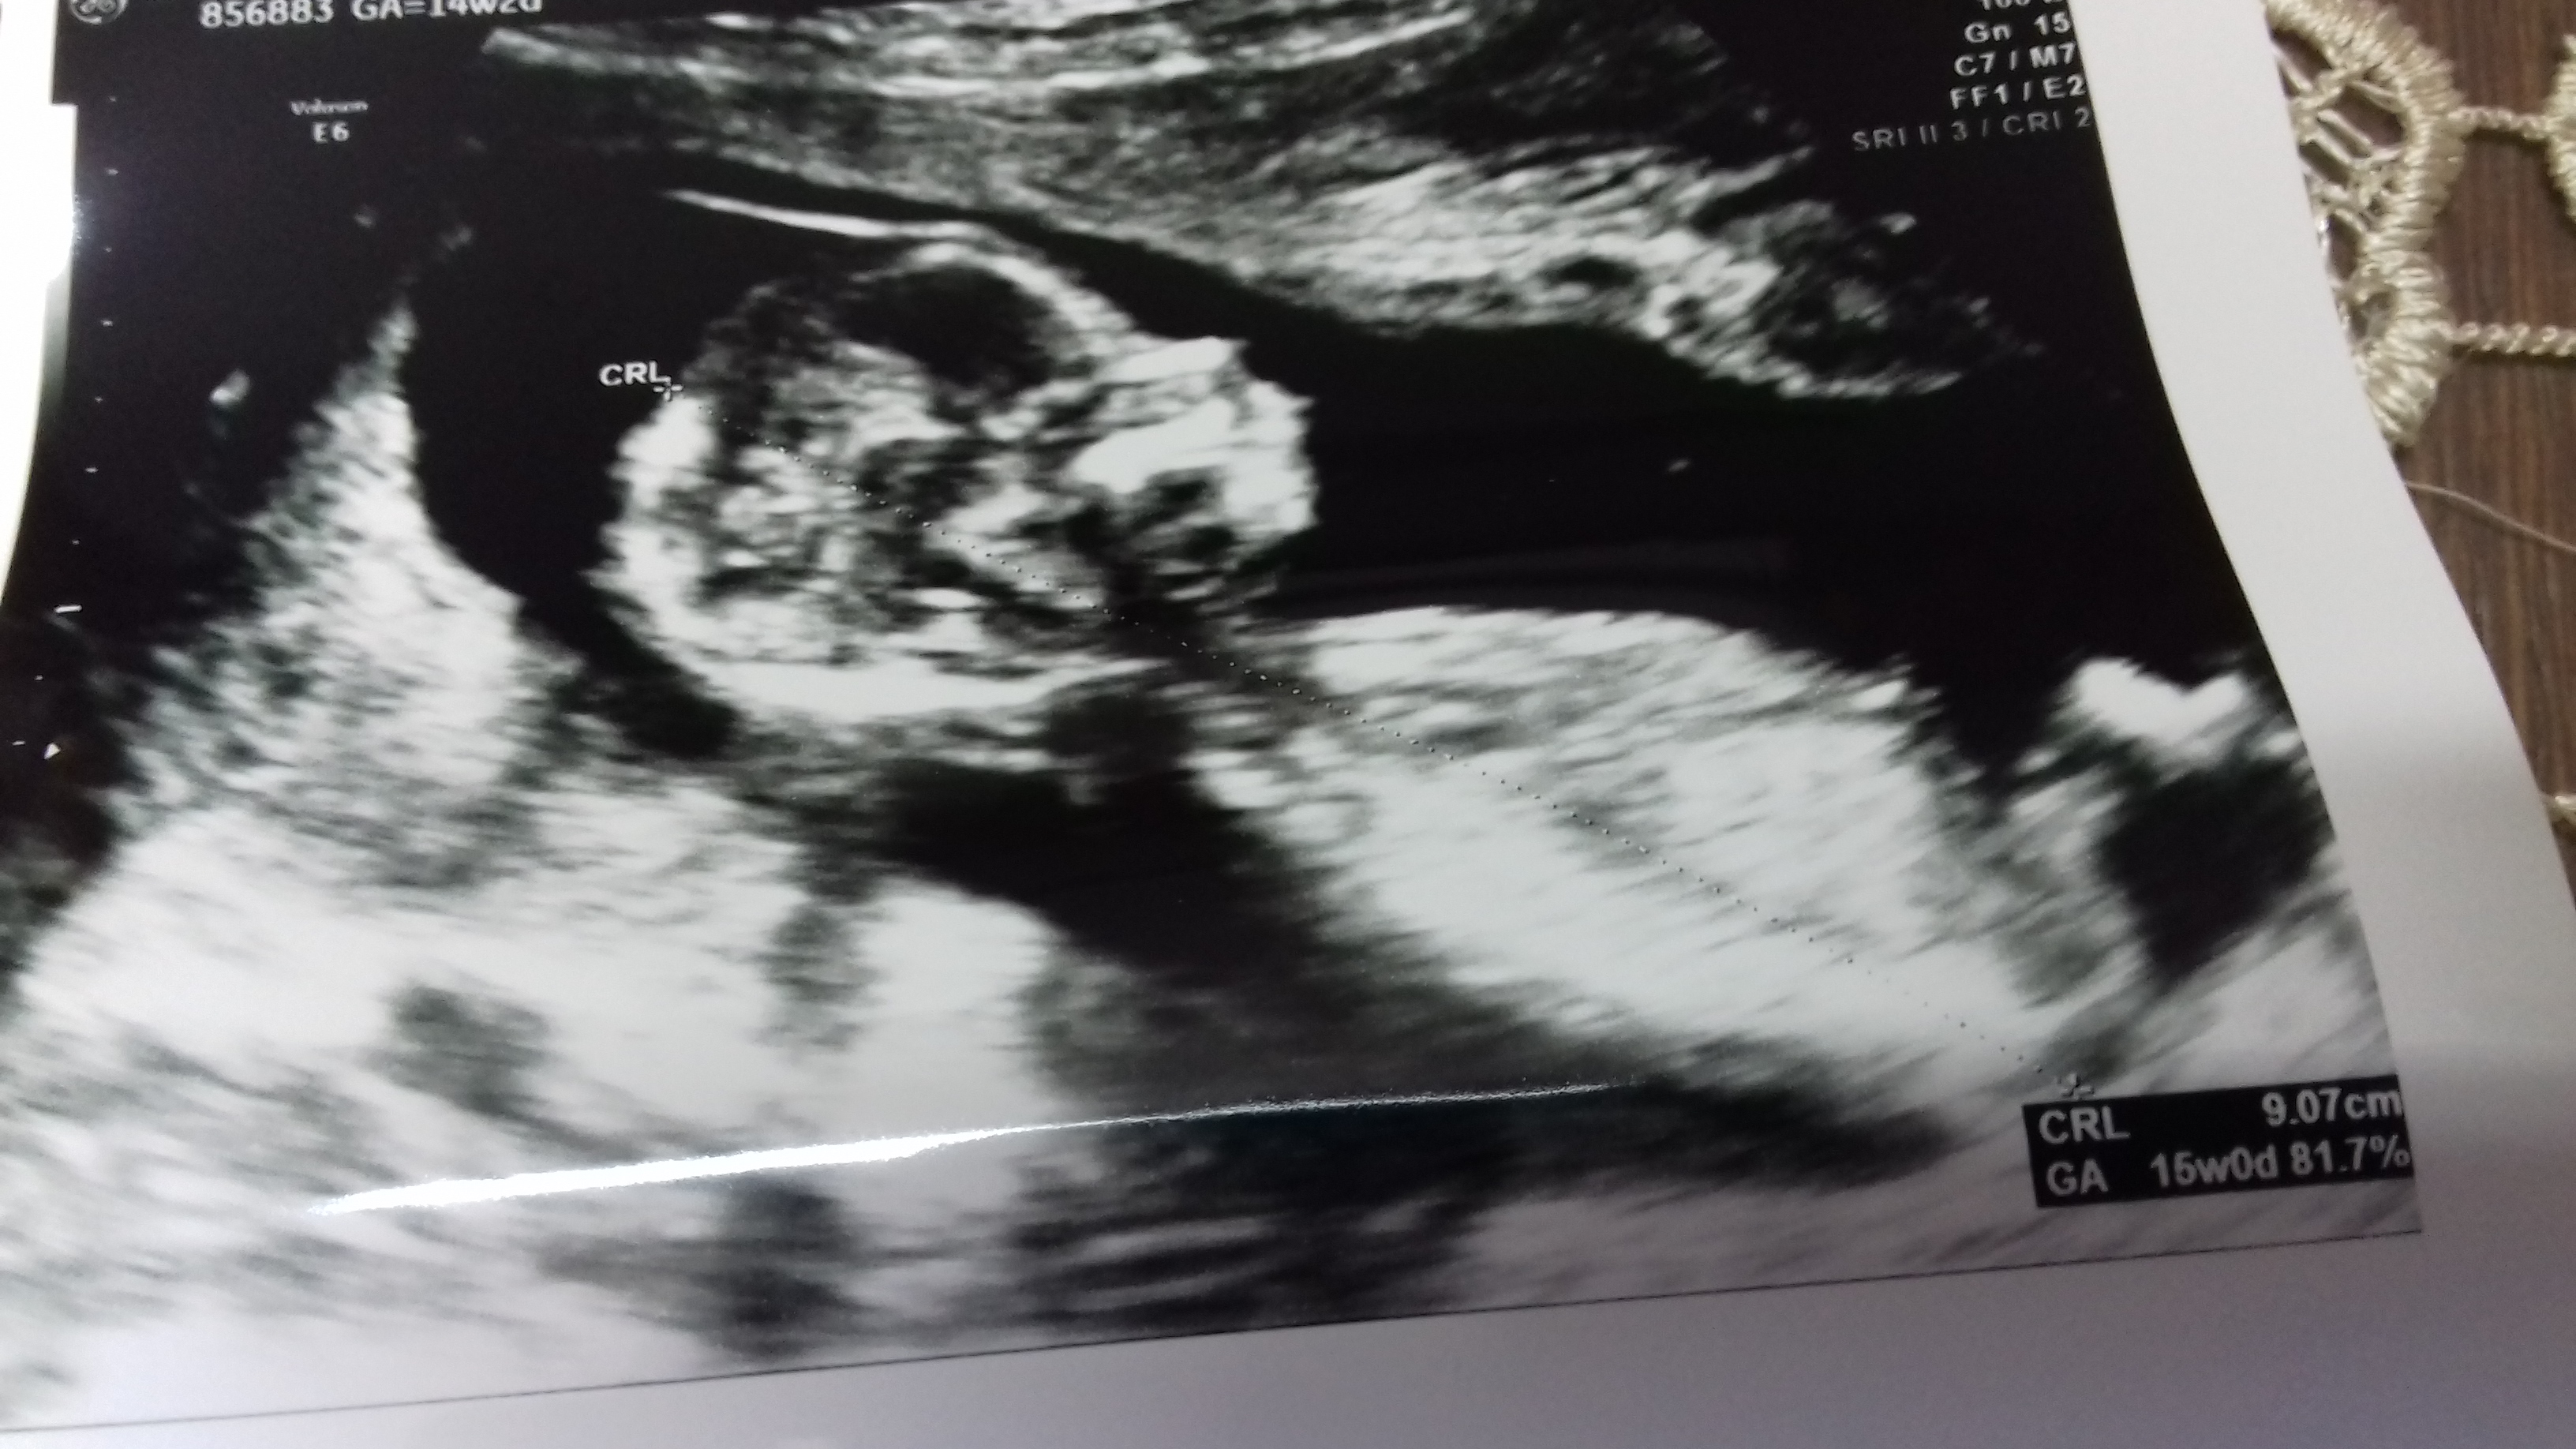

Thoughts please? I already have 3 boys. I wish it is a girl this time but i wont be disappointed either way xx

It's say on the photo 14 weeks 2 days! X

Yes 14+2. Thank you:) i do hope so. Have you looked at the potty scan as well? Thats confusing...You do have 3 sons as well and pregnant with your 4th baby? :)

I'm leaning girl. What gestation are the most recent pics from? If they are 13+ weeks, then I would most definitely say girl.